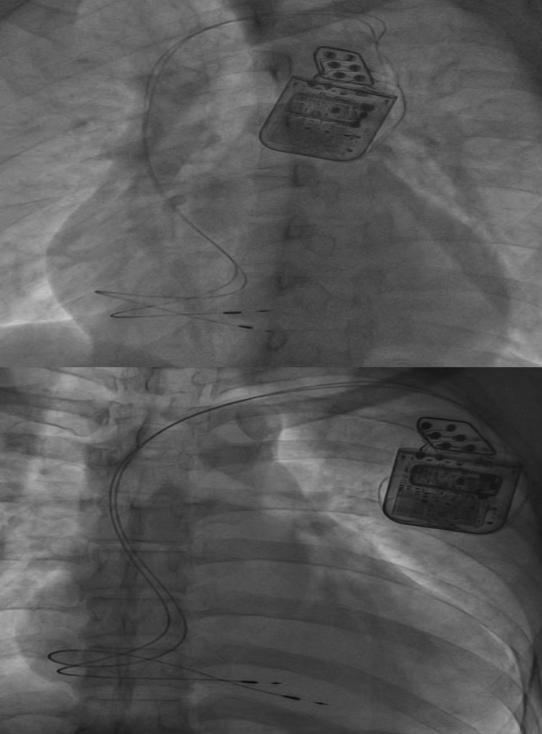

(图为CCM植入图)